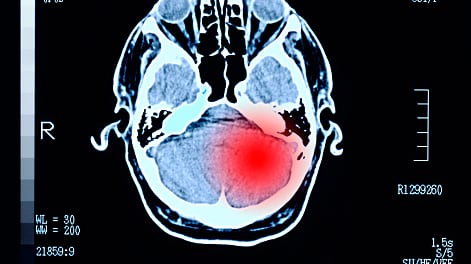

La tomografía computarizada reveló un tumor cerebral de gran tamaño. Los médicos informaron a la familia que Marcus tenía pocas horas de vida sin una cirugía de emergencia. Se organizó de inmediato una intervención quirúrgica que duró 12 horas, logrando extirpar el 98% del tumor.